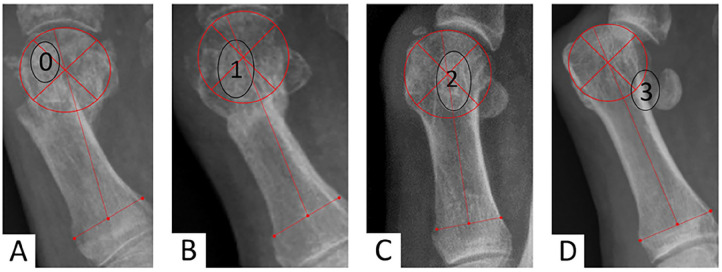

Methods: This retrospective study analyzed 116 feet that underwent percutaneous distal metatarsal transverse osteotomy with lateral soft tissue release and provisional Kirschner wire fixation, with a mean follow-up of 27.1 months, limited to severe cases (hallux valgus angle [HVA] > 40 degrees). Radiologic assessments included preoperative and postoperative measurements of HVA, intermetatarsal angle (IMA), distal metatarsal articular angle, sesamoid position, first metatarsophalangeal (MTPI) joint congruency, metatarsal length, and sagittal position. Clinical evaluations used the AOFAS scale, documenting the recurrence rate, the nature of complications, reoperations, and the association between them. Patient satisfaction was assessed through self-reported evaluations.